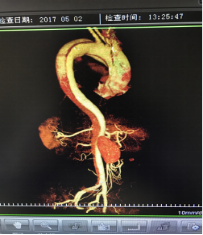

5月2號劉大伯照常早起干活,突然胸部劇烈疼痛,難以忍受,全身大汗,同時伴有右上肢發(fā)涼,他心想這次心絞痛比之前嚴重的多啊,趕緊叫上孩子到吉林國文醫(yī)院心血管內科住院,患者長期高血壓病史,血壓一直控制不理想,大夫給他做了檢查,測左上肢血壓:82/45mmHg,右上肢血壓測不出,心率52次/分,右側肱動脈、尺動脈、橈動脈搏動消失,左側股動脈搏動較右側弱?!霸懔耍p側血壓差別這么大,是不是主動脈夾層了?”,接診大夫趕緊找來李主任,李主任反復詢問患者病情,表情突然凝重起來,患者胸痛這么明顯,血壓低的厲害,主動脈夾層的可能性很大。二話不說,李主任立即聯(lián)系影像科的醫(yī)生準備做主動脈CTA,移動患者做檢查的過程大夫們非常小心,嚴密監(jiān)測患者血壓變化情況。兩個小時后結果出來了,主動脈夾層從升主動脈一直撕裂到左側髂總動脈!?。?/p>

李主任詳細的與劉大伯的女兒交代了病情,手術是挽救生命的唯一辦法,為了劉大伯的一線生機,我們積極聯(lián)系了我省權威的心血管外科,并做了詳細的匯報,兩家醫(yī)院對此非常重視,為劉大伯開通了綠色通道,安全的把他總到上級醫(yī)院,當天便給他進行血管置換及覆膜支架植術。他術后恢復的很好,后來劉大伯的女兒看望我們,感嘆道:沒想到國文醫(yī)院心內科應急能力這么高,在那么短的時間內診斷明確,才給了我的老父親手術的機會。